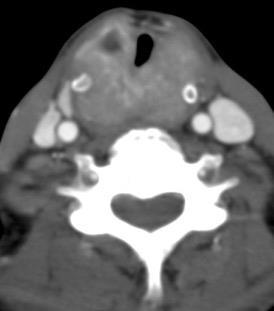

Carcinoma subglótico

Tumor poco frecuente. 1,8% de los tumores laríngeos.

Tendencia a invadir el anillo cricoideo y el esófago.

Ganglios + frecuentes

Mac Neill SD et al. Survival of patients with subglottic squamous cell carcinoma. Curr Oncol. 2018